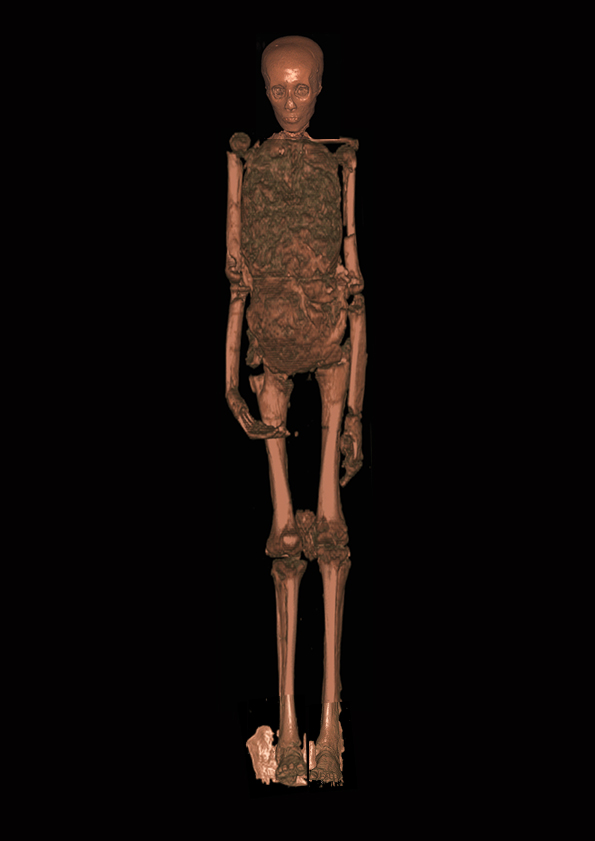

Nel complesso l’altezza della mummia risultò di 1,63 m, ma dalla lunghezza delle ossa degli arti è stato calcolato che Tutankhamon fosse alto 1,68 metri – un’altezza compatibile con quella delle due statue-guardiano all’ingresso della camera sepolcrale che lo raffigurano. L’età calcolata dalla ossificazione delle epifisi delle ossa lunghe risulta tra i 18 ed i 20 anni al momento della morte.

Gli arti del Faraone erano stati fasciati singolarmente prima di essere richiusi nella fasciatura esterna. Le braccia flesse sull’addome, e non incrociate sul petto, in posizione nettamente anomala per un Faraone egizio; l’avambraccio sinistro più in alto del destro ed entrambi ricoperti di braccialetti. Dita di mani e piedi erano avvolte in guaine d’oro su cui erano riprodotte le unghie e le prime falangi; i piedi calzati con sandali d’oro lavorati a sbalzo per imitare una suola di giunchi intrecciati.

La mummia fu riesumata pesantemente danneggiata. La cassa toracica sfondata, mancavano lo sterno, diverse costole, le clavicole; le palpebre asportate, il pene disperso (ritrovato anni dopo). Le braccia erano in posizione distesa lungo i fianchi e non più incrociate sull’addome. Era stata rubata la calottina che copriva il cranio. Nessuno sa cosa sia successo, né è facile fare delle ipotesi. Il corpo era stato fotografato ricomposto al momento della nuova tumulazione nel sarcofago, ed era apparentemente integro.

Le prime immagini della TAC